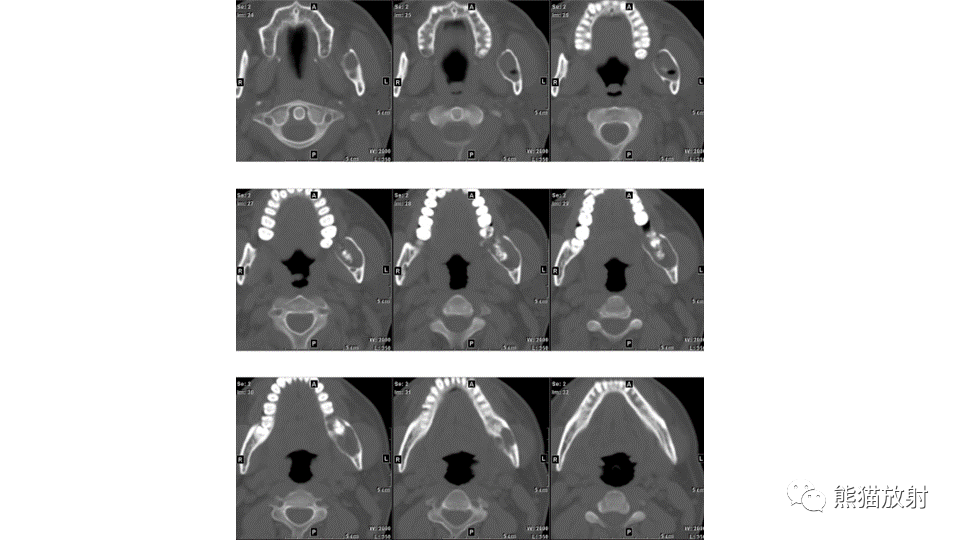

【病例】下颌骨成釉细胞瘤2例CT-1

【病例】下颌骨成釉细胞瘤2例CT-2

【病例】下颌骨成釉细胞瘤2例CT-3